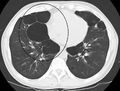

A chest X-ray and complete blood count may be useful to exclude other conditions at the time of diagnosis.[61] Characteristic signs on X-ray are overexpanded lungs, a flattened diaphragm, increased retrosternal airspace, and bullae while it can help exclude other lung diseases, such as pneumonia, pulmonary edema or a pneumothorax.[62] A high-resolution computed tomography scan of the chest may show the distribution of emphysema throughout the lungs and can also be useful to exclude other lung diseases.[15] Unless surgery is planned, however, this rarely affects management.[15] An analysis of arterial blood is used to determine the need for oxygen; this is recommended in those with an FEV1 less than 35% predicted, those with a peripheral oxygen saturation of less than 92% and those with symptoms of congestive heart failure.[14] In areas of the world where alpha-1 antitrypsin deficiency is common, people with COPD (particularly those below the age of 45 and with emphysema affecting the lower parts of the lungs) should be considered for testing.[14]

A severe case of bullous emphysema

Axial CT image of the lung of a person with end-stage bullous emphysema.